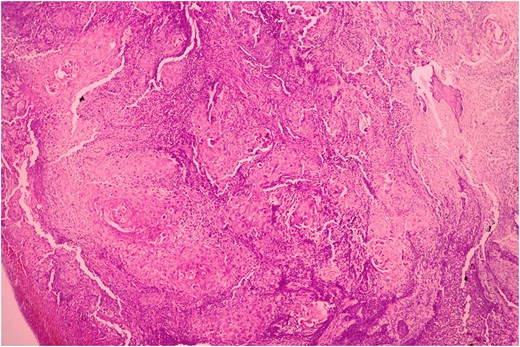

Biopsy was taken from hypertrophied and ulcerated lesion. On microscopy, tissue was lined by keratinized stratified squamous epithelium with surface ulceration. Underlying stroma showed infiltrating squamous cell carcinoma (SCC) along with extensive collagenous fibrosis (Fig. 2). Dense acute and chronic inflammations were also noted. A diagnosis of SCC with familial gingival fibromatosis was given (Fig. 3).

Histopathological picture showing infiltrating squamous cell carcinoma along with bundles of collagenous fibrous connective tissue. (H&E, ×400).